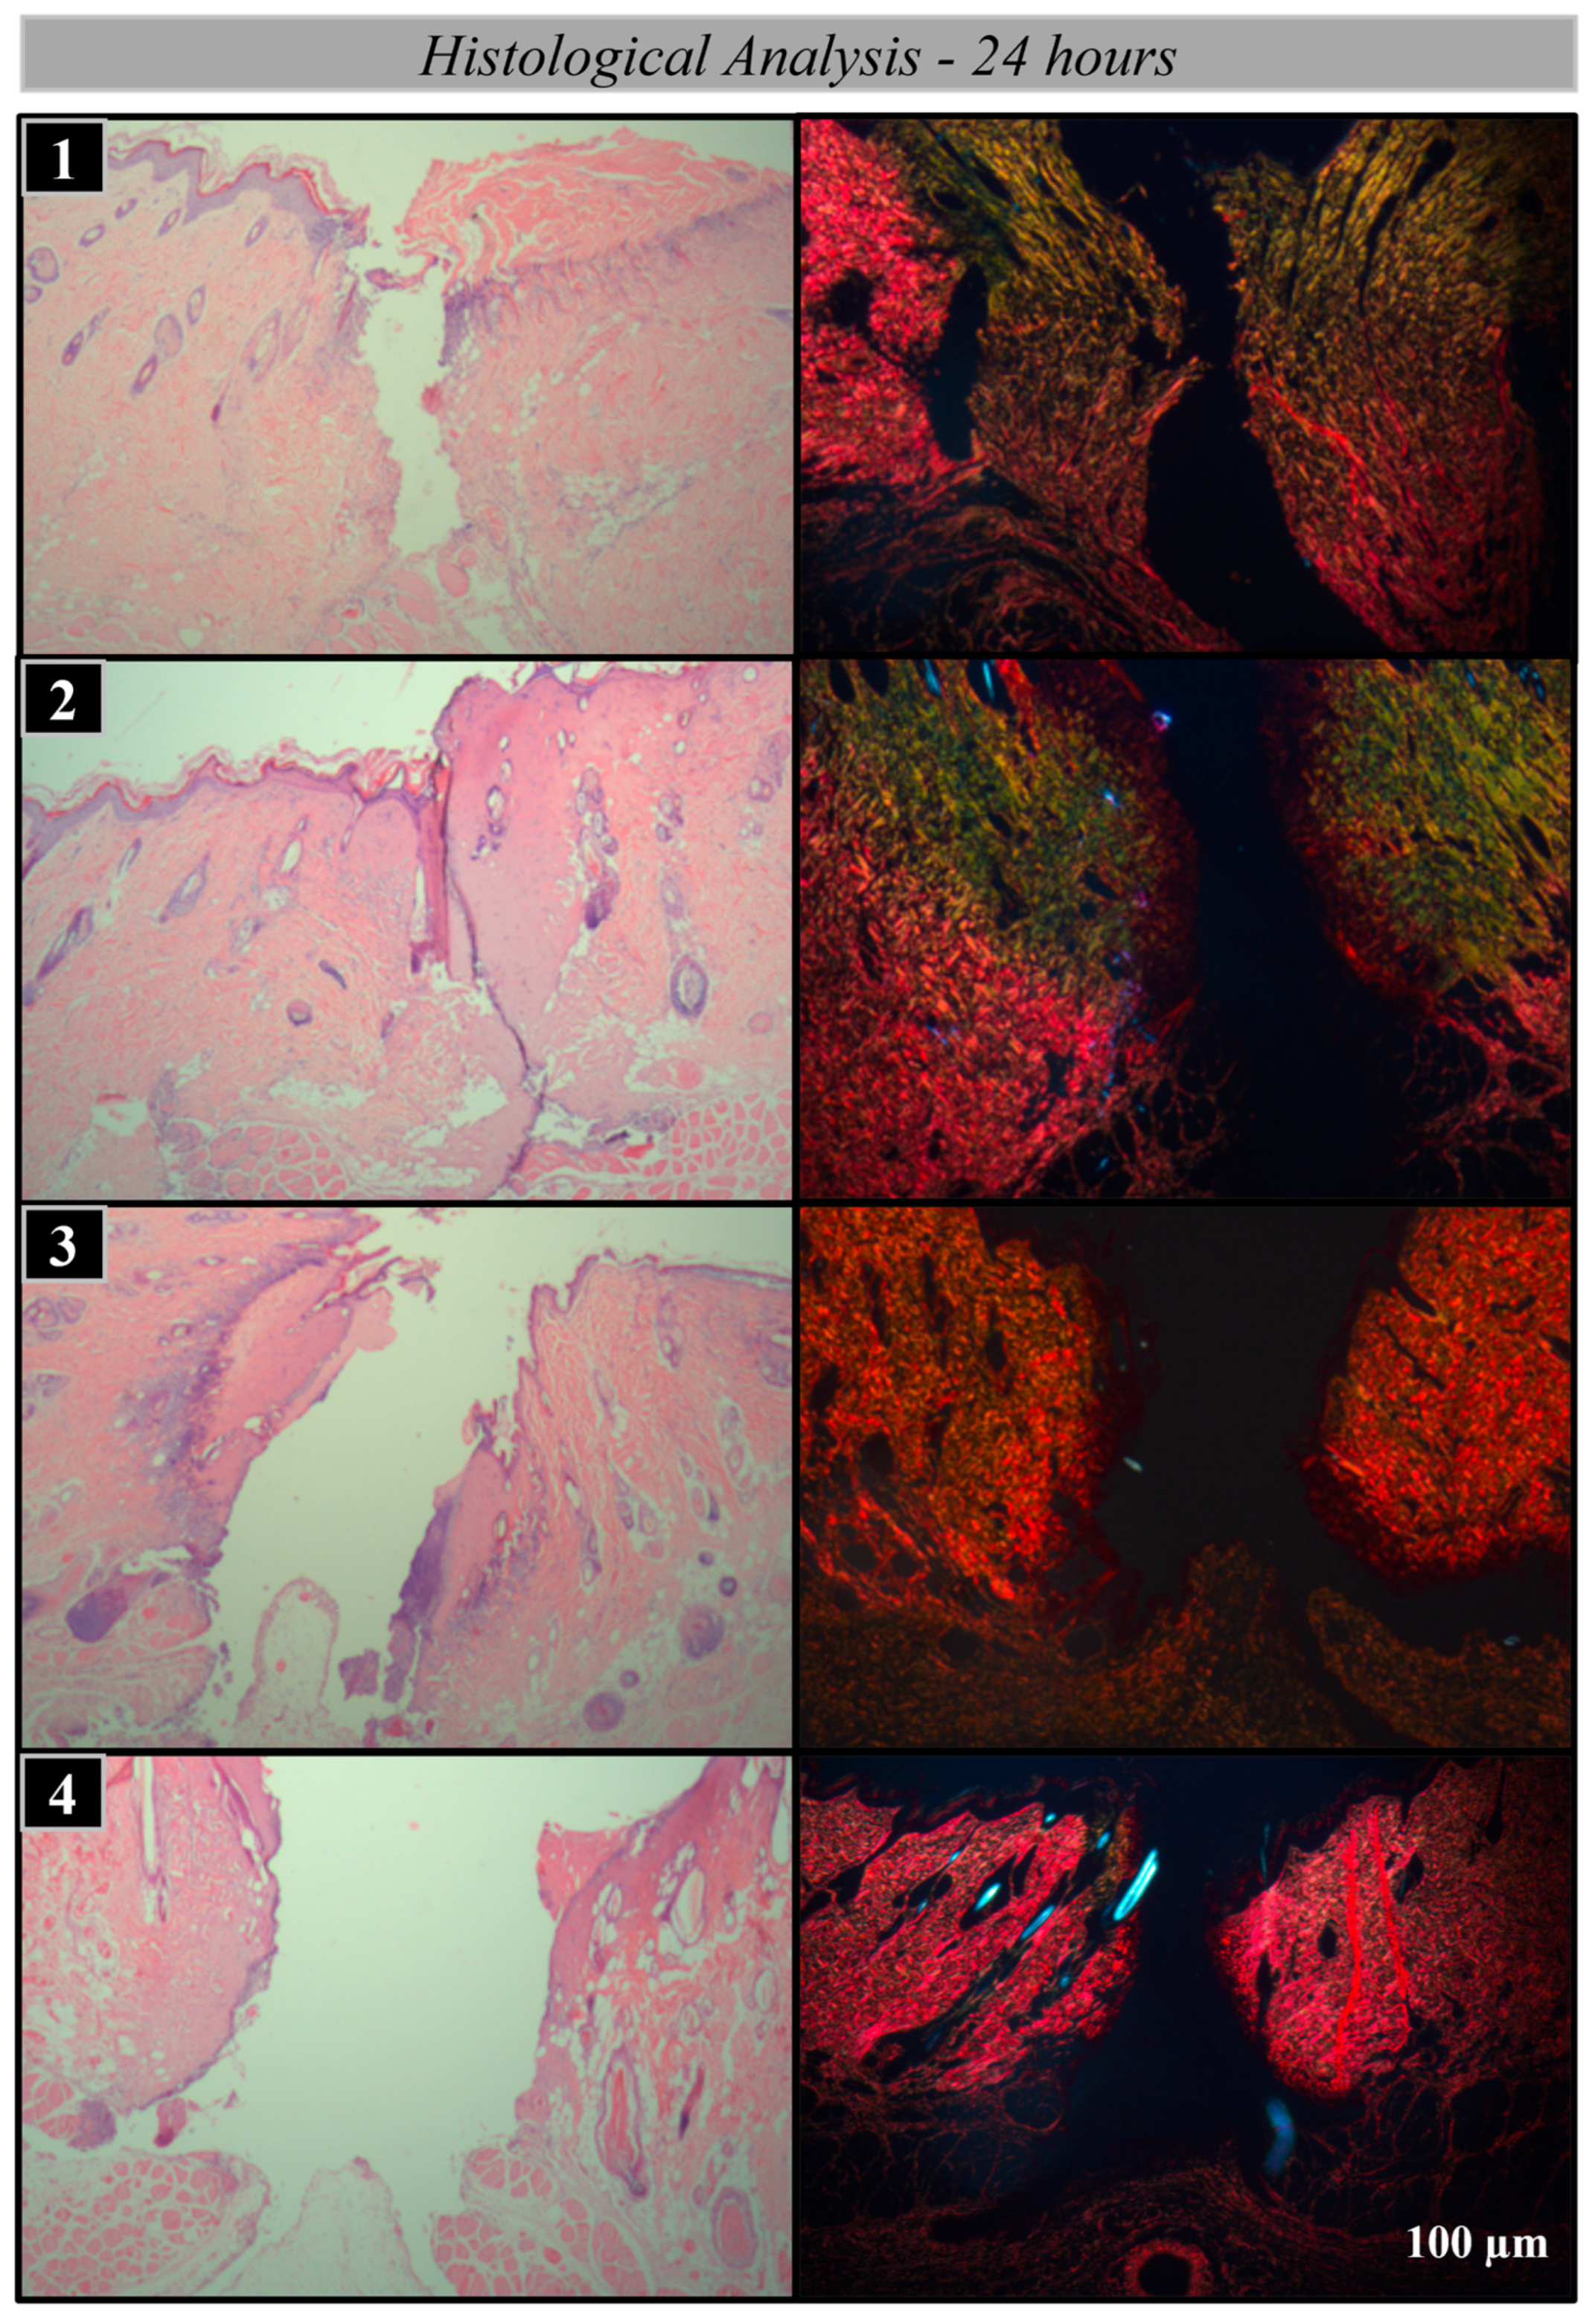

Histological and Histomorphometric Analysis